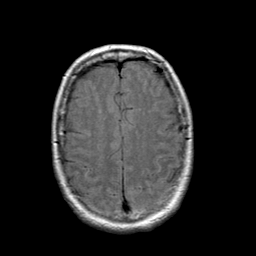

Stroke: proton density-weighted MR #1 -- Slice #19

[Home][Help][Clinical] Slice 19